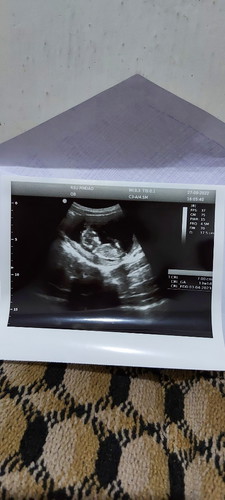

Usg 13w masya Allah bahagia banget bun lihat perkembangan babynya,terharu krna hamil pertama..

Kalau 4D usg nya sktar 4 bln mungkin udh bisa ketauan apa ya,sya 13w jga tpi blm usg tggu 4 bln spa tau klu usg 4D udh bsa kelihatan

Alhamdulillah saya juga Minggu kemarin USG di usia 13w6d buah hati sudah lincah bergerak kesana kesini ❤️🥰😍